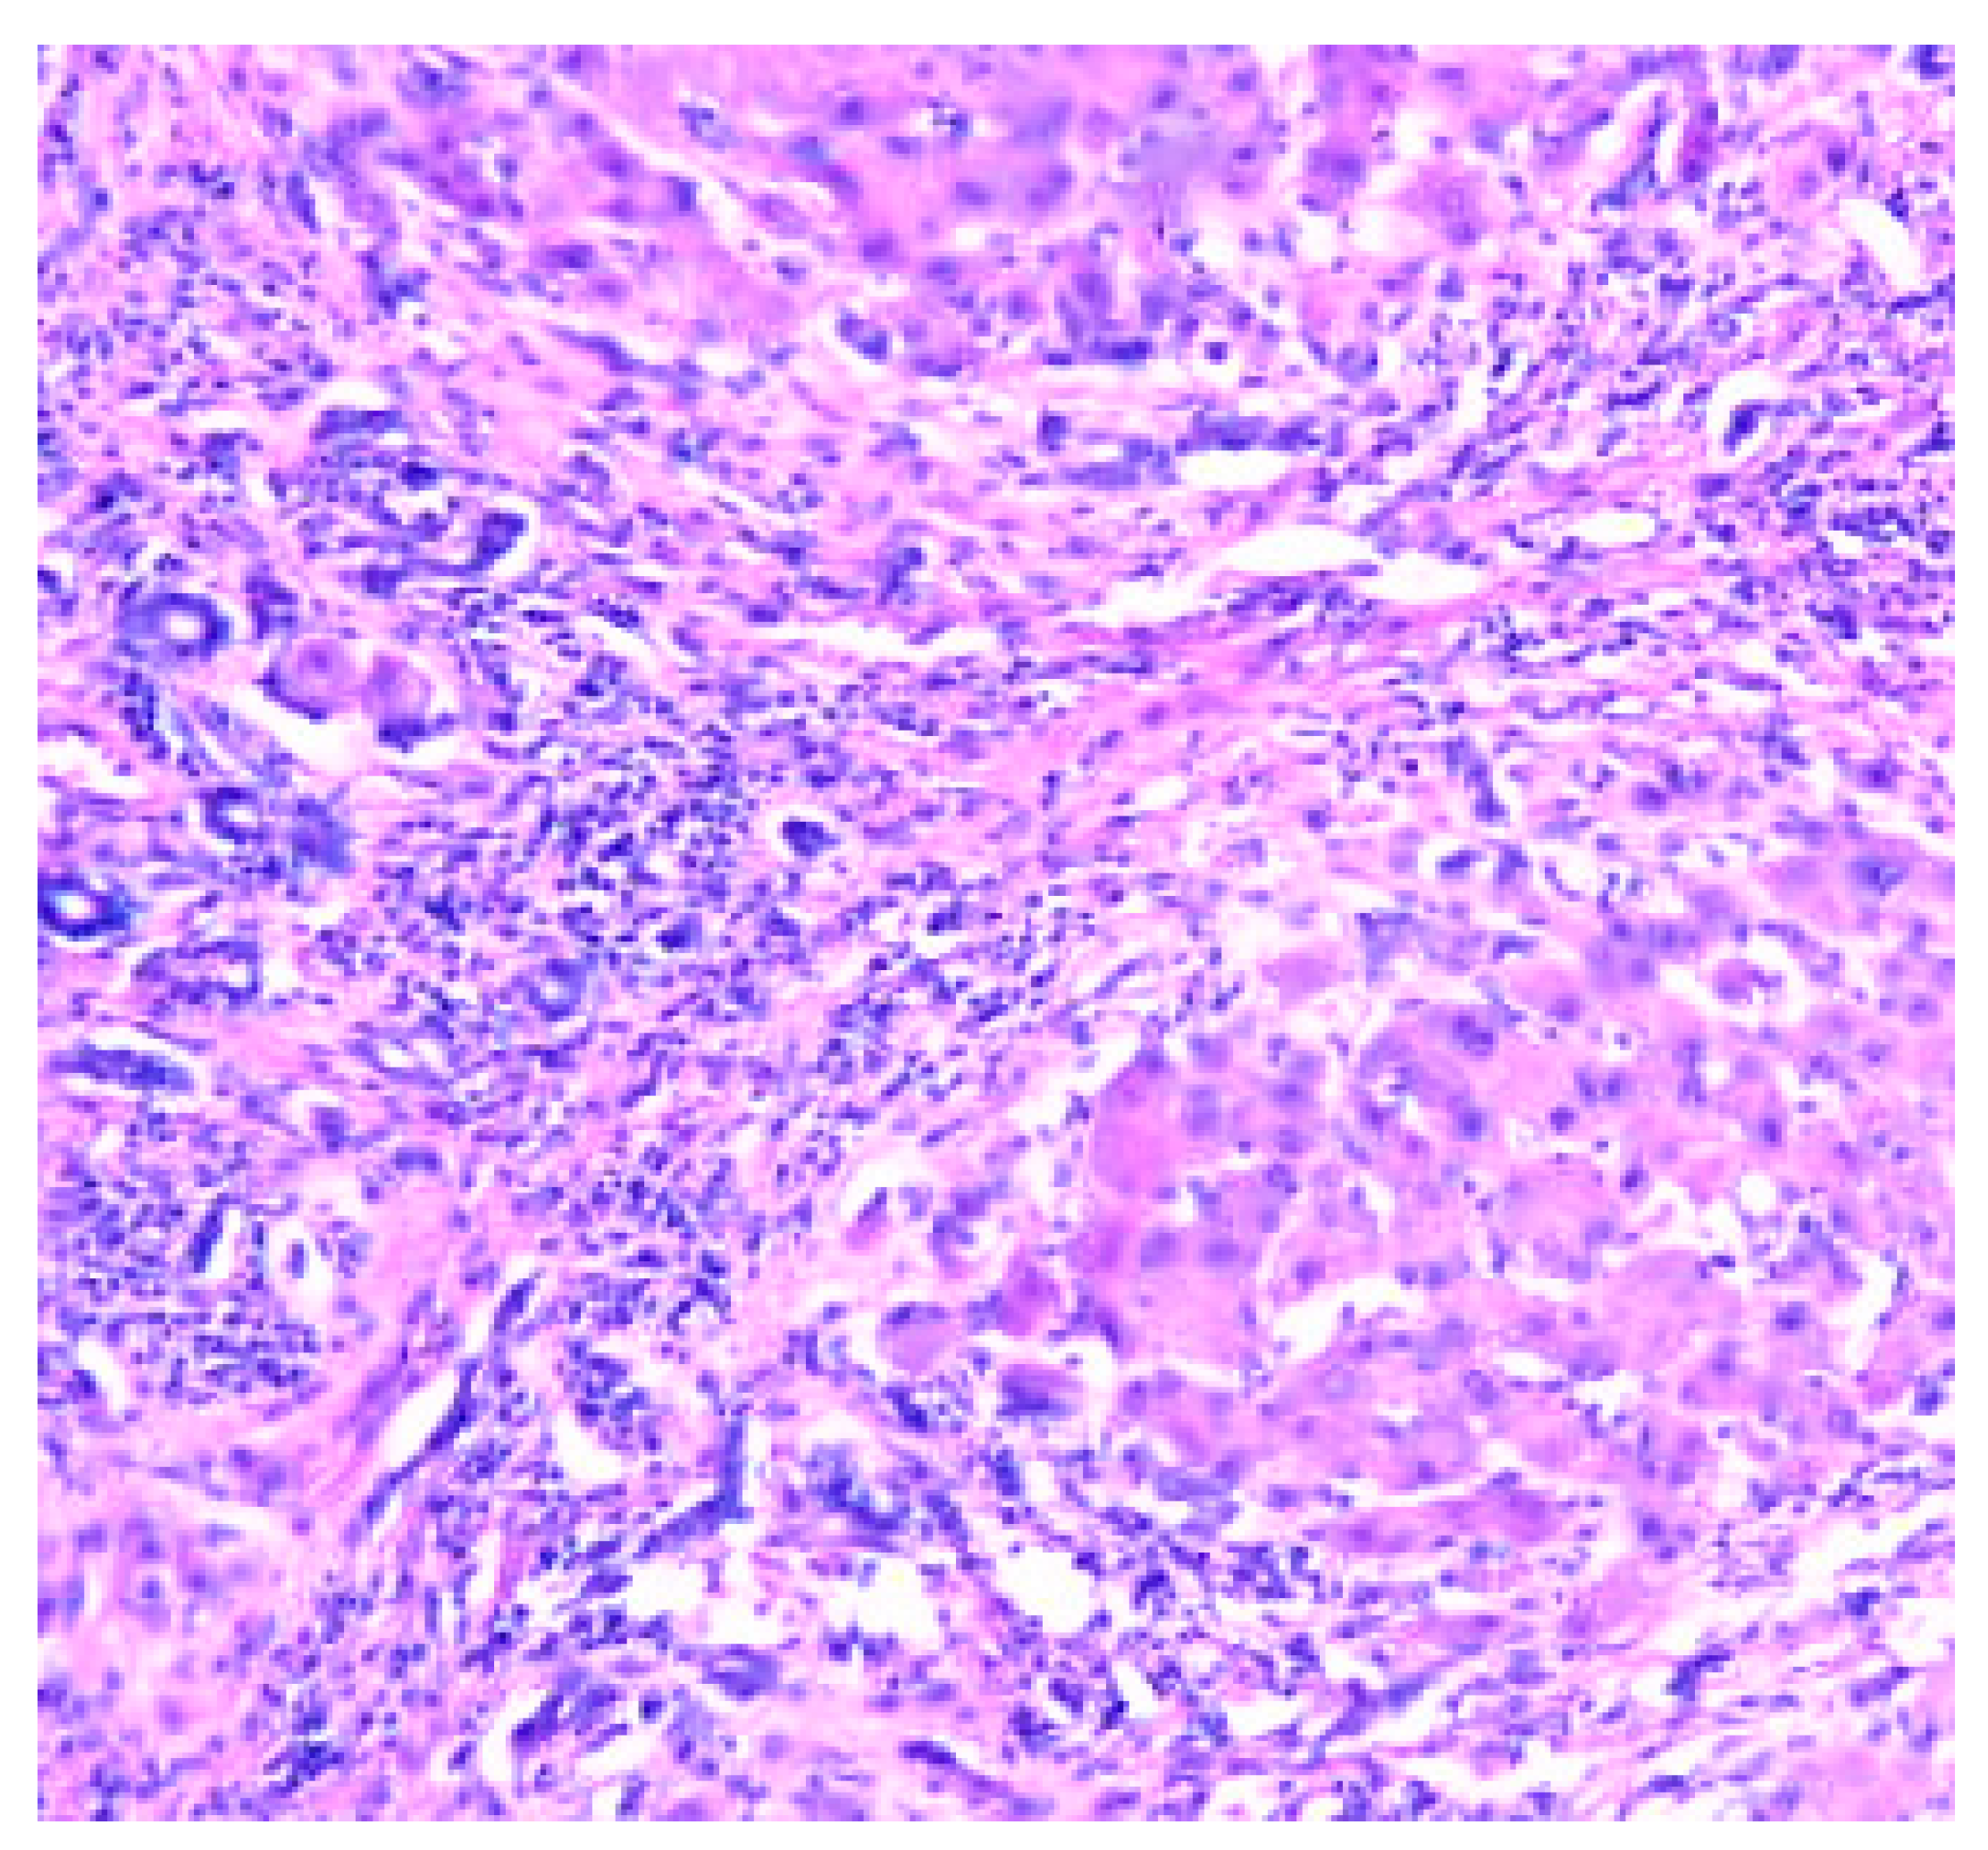

- Zone I is considered to be the periportal region of hepatocytes and are the best perfused and first to regenerate due to their proximity to oxygenated blood and nutrients. Implication in oxidative metabolisms.

- Zone II is defined as the pericentral region of the hepatocytes.

- Zone III has the lowest perfusion due to its distance from the portal triad. Implication role in detoxification.